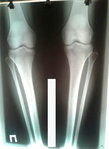

Исходник - 40 лет.

Дата операции 28 04.2017г.